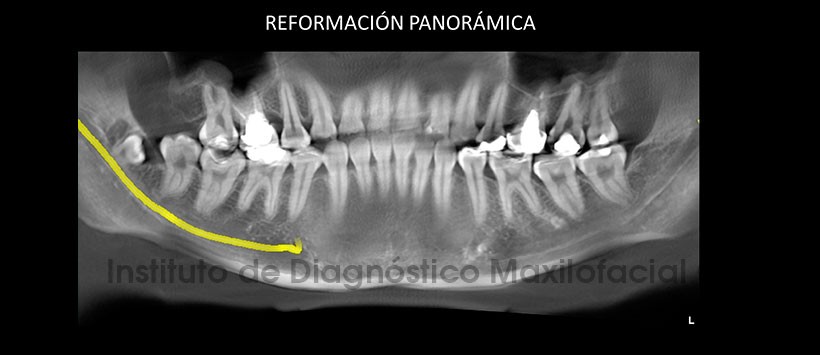

A la evaluación de la tomografía volumétrica (CBCT), en la reformación panorámica (Figura 2), en los cortes transaxiales (Figura 3) y tangenciales (Figura 4), se evidencia supernumerario en posicipon mesioangular con el segmento coronario hacia lingual, segmento radicular hacia la tabla ósea vestibular. Ápices en estrecha relación con el conducto dentario inferior.